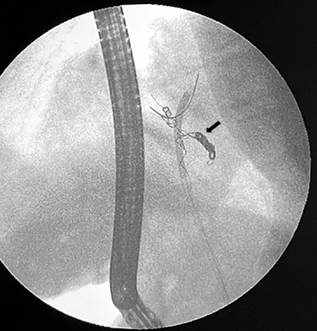

In May 2022, the patient presented with jaundice. An ERCP was performed, revealing a 15 mm stone in the left hepatic lobe, which could not be extracted. Therefore, electrohydraulic lithotripsy via choledochoscopy was scheduled. During this procedure, multiple choledocholithiasis was identified in relation to migrated foreign bodies (coils) in the biliary duct (Figures 1 and 2). The stones and most of the visible coils were successfully removed, a biliary stent was left, and a new endoscopic procedure was scheduled. However, the patient reconsulted for another episode of cholangitis, and a medical board decided to perform a biliary-enteric bypass as definitive management.